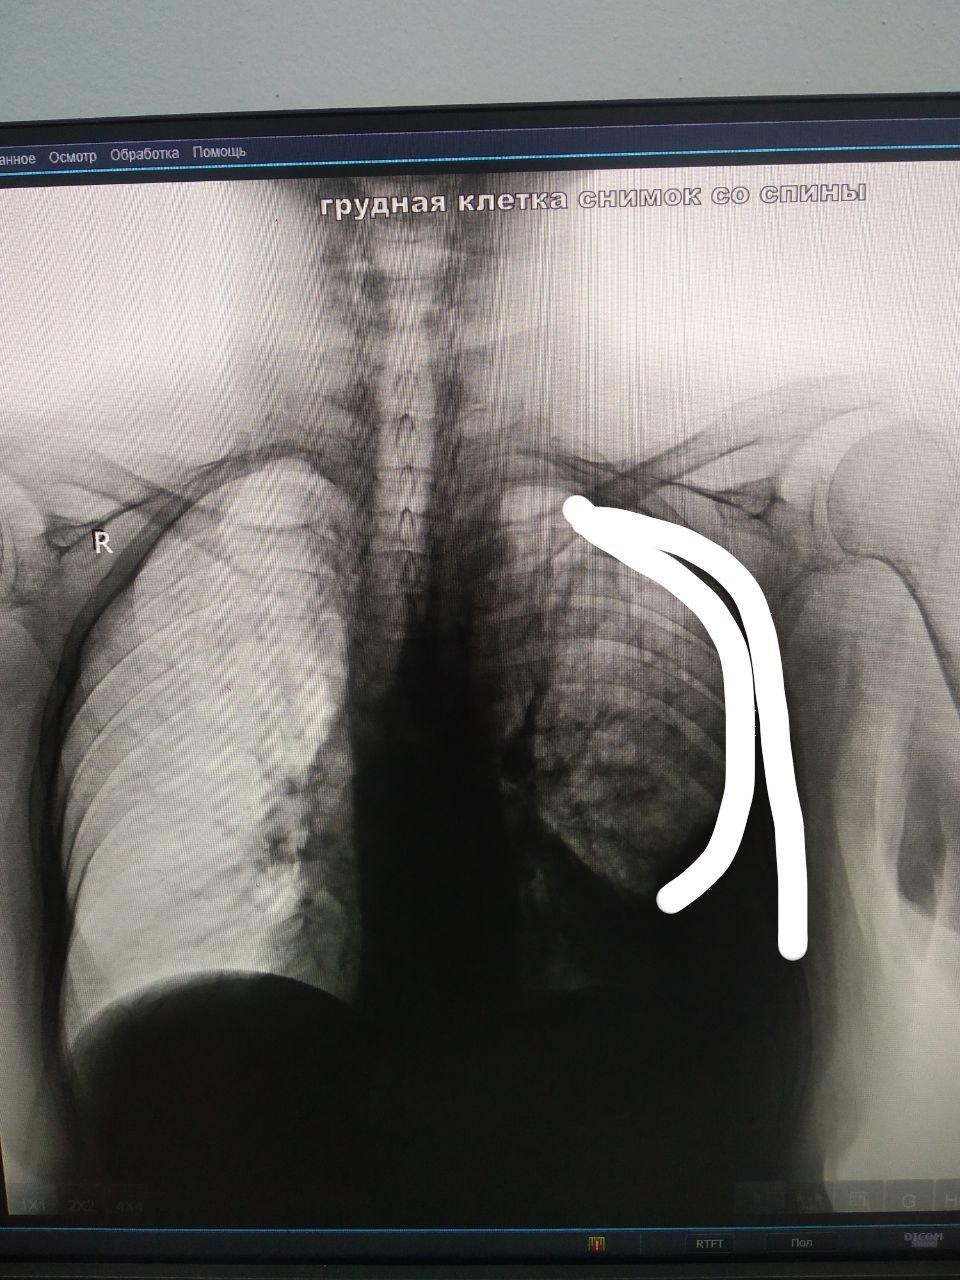

Malohat Jumayeva in Radiology/Рентгенология Чат

Bolnaya 1938-goda, prosta kashel i odishka.

Плевропневмония слева

Просто пневмония такое затенение интенсивное не даст

А тут не воздух случаем по типу пневмоторакса?

Осумкованный плеврит и пневмонии

вот те и заключение